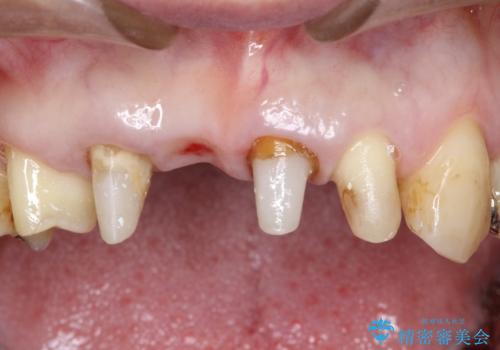

①保存不可の歯の抜歯・根管治療

②矯正治療

③セラミックの装着

という流れで行いました。

1年程度の治療期間が必要となりましたが、仕上がりには患者様に満足していただけました。